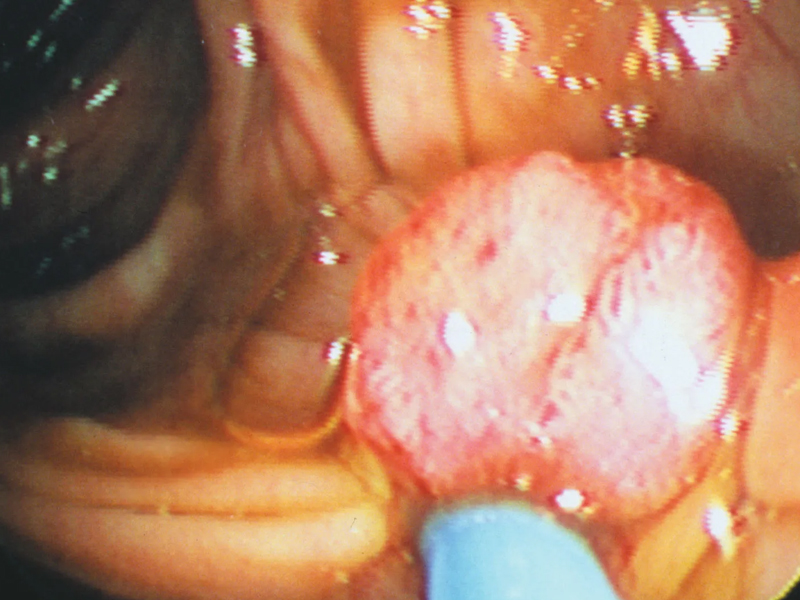

癌症不是一日就長成的,有一個相當長的過程。很多癌症有癌前狀態,有一些良性病變其實是惡性腫瘤的“前奏”,如不重視,任其發展下去,有可能演變成癌症。 小病不治成大病,所謂大病者,其中之一就是惡性腫瘤。以下幾種小病不重視可能拖成癌症。 1、慢性炎症 ① 反流性食管炎增加食管癌風險。 ② 慢性萎縮性胃炎有發展為胃癌的風險。 ③ 慢性潰瘍性結腸炎(據估計有 3%~5% 的潰瘍性結腸炎發生大腸癌,潰瘍性結腸炎史 20 年,發生癌變者 12.5%,30 年時達 40%)。 ④ 慢性肝炎,病毒性肝炎(主要是慢性乙肝和丙肝)是原發肝細胞肝癌的主要危險因素,其他酒精性肝炎、藥物性肝炎也是危險因素。 ⑤ 慢性胰腺炎,可損傷胰腺實質,反復發生可使胰腺癌發病率上升。 ⑥ 膽道系統慢性炎症,是膽囊癌膽管癌的危險因素。長期慢性膽囊炎引起的磁性膽囊,22% 存在膽囊癌。西方國家原發性硬化性膽管炎是膽管癌最重要的危險因子,8%~40% 的原發性硬化性膽管炎患者合併膽管癌。 ⑦ 膀胱感染(寄生蟲、細菌、真菌或病毒感染)可能增加膀胱癌風險。 ⑧ 前列腺的慢性炎症,可導致細胞過度增殖以修復病變組織,易形成感染相關性癌症。流行病學研究顯示患性病或前列腺炎病史的患者,患前列腺癌的風險明顯增高。 ⑨ 包皮陰莖頭慢性炎症,是陰莖癌的發病危險因素。 2、慢性阻塞性肺疾病 研究表明,有慢性支氣管炎者,肺癌發病率高於無慢性支氣管炎者(幾乎2倍)。其他如肺結核病史、肺炎和肺氣吸等都和肺癌有一定的關聯。 3、胃腸道息肉 有大約 15%~40% 的結腸癌源於結腸多發性息肉,其癌前期病程約為 5~20 年;腺瘤可以癌變,直徑小於 1cm 者癌變率低於 2%,直徑大於 3cm 癌變率超過40%。而如果是家族性腺瘤性息肉病(FAP)患者,25 歲時惡變率為 9.4%,30 歲為 50%,50 歲以前幾乎 100% 惡變,中位惡變年齡為 36 歲。 4、結石 膽管結石,膽囊結石是膽管癌膽囊癌的主要危險因素之一。膽囊結石和膽囊癌之間有很強的關聯性,75% 的膽囊癌患者合併膽囊結石,直徑超過 3cm 的膽囊結石患者,膽囊癌風險上升 10 倍。 膀胱結石可能增加膀胱癌風險。 5、白斑性病變 口腔黏膜白斑或紅斑是口腔癌的風險因素。外陰白斑可能是外陰癌的風險因素之一。 6、潰瘍性病變 胃十二指腸潰瘍可能發展為胃癌。口腔潰瘍經久不愈要警惕口腔癌。任何部位的潰瘍如果經久不愈,都要提高警惕。 |